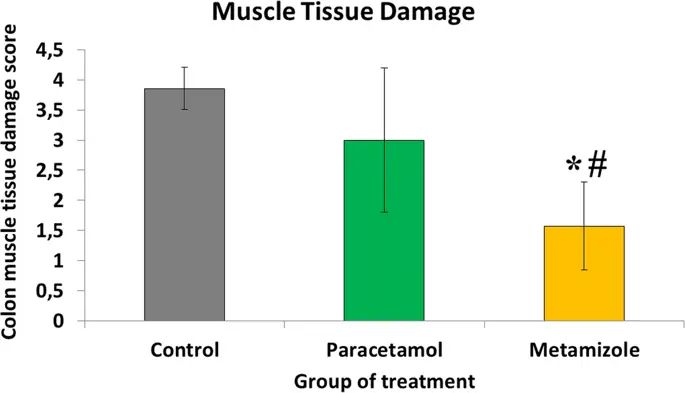

Гистопатологические данные показали больше неудач анастомоза в группе метамизола по сравнению с парацетамолом и контрольной группой ( рис. 1 ). Повреждение мышечных слоев, а также воспалительных тканей и грануляции, которые имели место в области анастомоза, оценивалось с использованием системы подсчета из гистологических образцов ( Рис. 2 ). Было обнаружено, что повреждение мышц в области анастомоза ободочной кишки было более тяжелым в группе метамизола (1, 57 ± 0, 8) по сравнению с парацетамолом (3 ± 1, 3) и контролем (3, 86 ± 0, 38) со значением р <0, 05. Парацетамол не имел негативных последствий повреждения мышц толстой кишки во время процесса анастомоза по сравнению с контролем (р> 0, 05).

Оценка повреждения мышечного слоя толстой кишки в области анастомоза (*, метамизол против контроля, р <0, 05; #, метамизол против парацетамола, р <0, 05). Низкие значения, указывающие на больший урон

Образование грануляционной ткани на толстом кишечнике анастомоза было более подавлено в группе метамизола (1, 71 ± 0, 5), чем в парацетамоле (3, 43 ± 0, 8) и контрольной группе (3, 86 ± 0, 4) (р <0, 05). Кроме того, образование грануляционной ткани было сопоставимо между парацетамолом и контрольной группой (р> 0, 05) ( рис. 3).